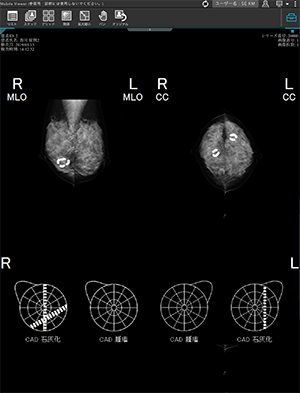

特長<4>

超音波検査の精度向上をサポートするシェーマリンク機能

CAD検出結果(コニカミノルタ社製)やMG画像上で指定した病変情報をエコーシェーマ上に反映し,シェーマ画像を作成。超音波検査時にタブレット端末等でシェーマ画像を確認できます。